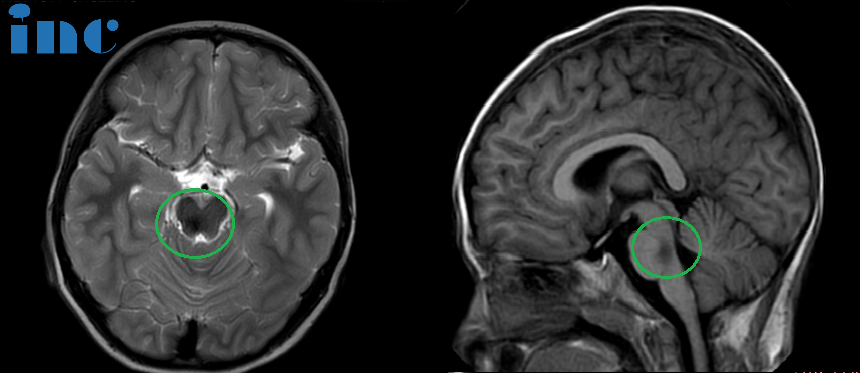

术后:头颅MR(蓝色区域) 显示小脑半球及脑干形态正常,中线结构居中,原脑桥内团块状信号消失。